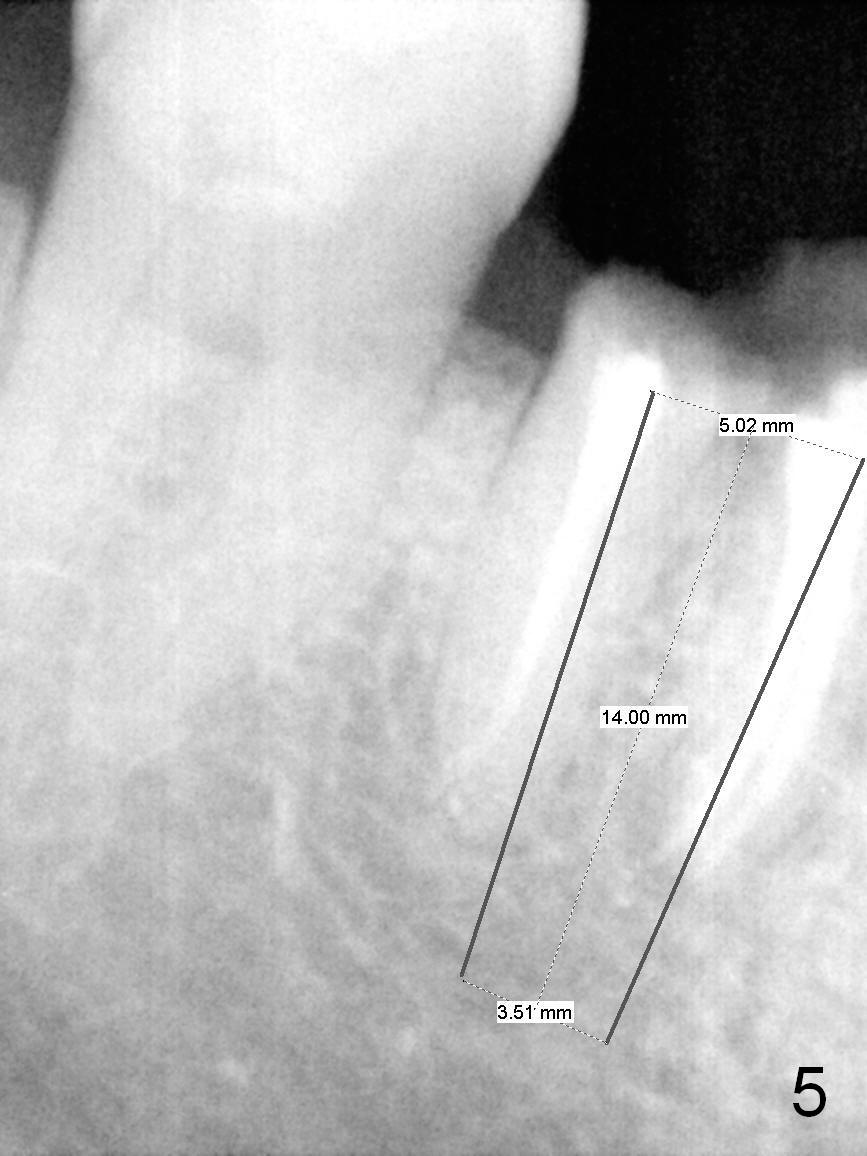

A 68-year-old lady (WQ) had CT taken 3 years ago (Fig.1-3), which show 3 roots (M: mesial; DB: distobuccal; DL: distolingual) of the lower right 1st molar and large caries (C).  Recently the tooth fractures after root canal therapy (Fig.4-6).

An implant placed the tripod septum should be stable.  The length of the initial osteotomy is 12 mm using 2 mm pilot drill.  Take intraop PA as early as possible for trajectory and depth determination.